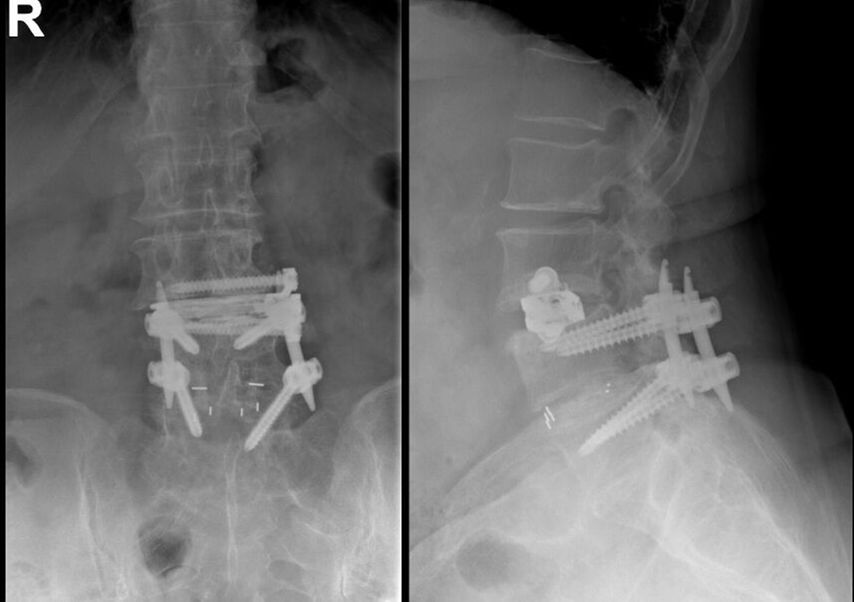

Beispiel für die Implantation zervikaler Pedikelschrauben. In diesem Fall kam es bei einem 61-jährigen Patienten 10 Jahre nach anteriorer zervikaler Diskektomie und Fusion (ACDF) C4/5 und ventraler Verplattung C4–6 zu einer Ankylosierung auch von C6/7. Nach Sturz kam es zu einer Fraktur bei C6/7 mit begleitender Bogenfraktur und auch Beteiligung der dorsalen Ligamenta (Abb. 1 und 2). Klinisch bestanden ausgeprägte Nackenschmerzen und kein neurologisches Defizit. Es wurde die Indikation der dorsalen Verschraubung von C4 auf Th1 gestellt. Intraoperativ wurde routinemäßig zusätzlich eine kleine Referenzschraube in einer Lamina – entfernt von der Dornfortsatz-Referenzklemme für die Navigation – gesetzt. Mit dieser konnte intraoperativ die Genauigkeit der Navigation exakt überprüft werden (Abb. 4 und 5). Mittels navigierter High-Speed-Fräse wurden die Schraubenkanäle vorgebohrt (Abb. 6), im Anschluss wurde der Bohrkanal ausgetastet und die Schrauben wurden implantiert. Abbildung 7 zeigt eine Röntgenkontrolle 3 Monate postoperativ.